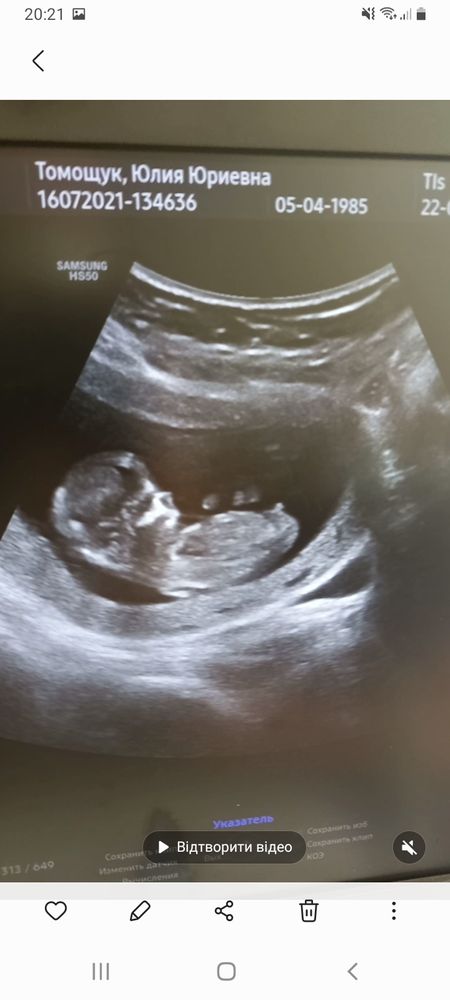

Вот и прошли мы первый скриннинг. В 12+1. По УЗИ все хорошо, даже на 3 дня опережаем срок по росту. Носовая косточка 2 мм, ТВП тоже в норме. Бусинка активно крутилась там во все стороны, махала ручками и ножками)

Вот думаю, кто же у меня там?) Мальчишка или девчуля? Сделала пару кадров с видео УЗИ. Половой бугорок то параллельно, то к верху, в зависимости от движений малыша)